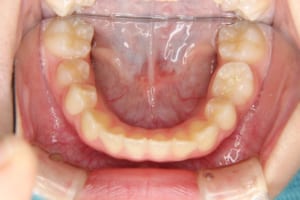

After

治療後